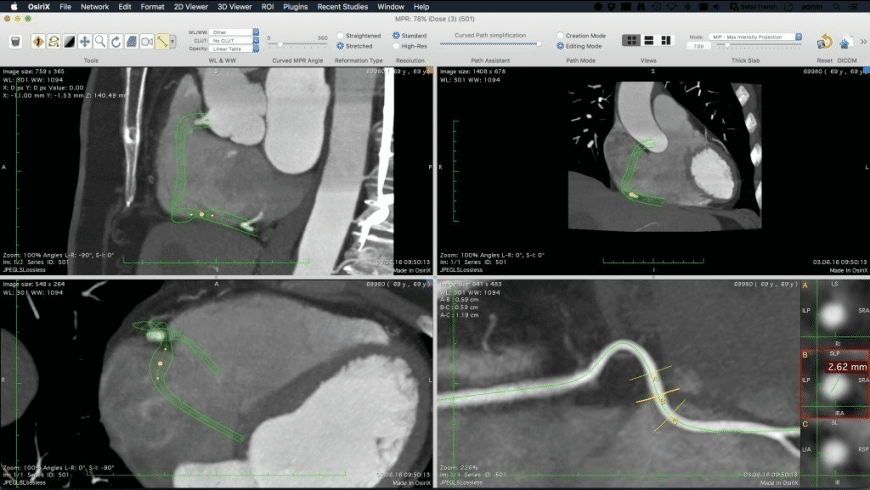

- Special 3 D MPR mode for displaying volume datasets in 3 orthogonal views